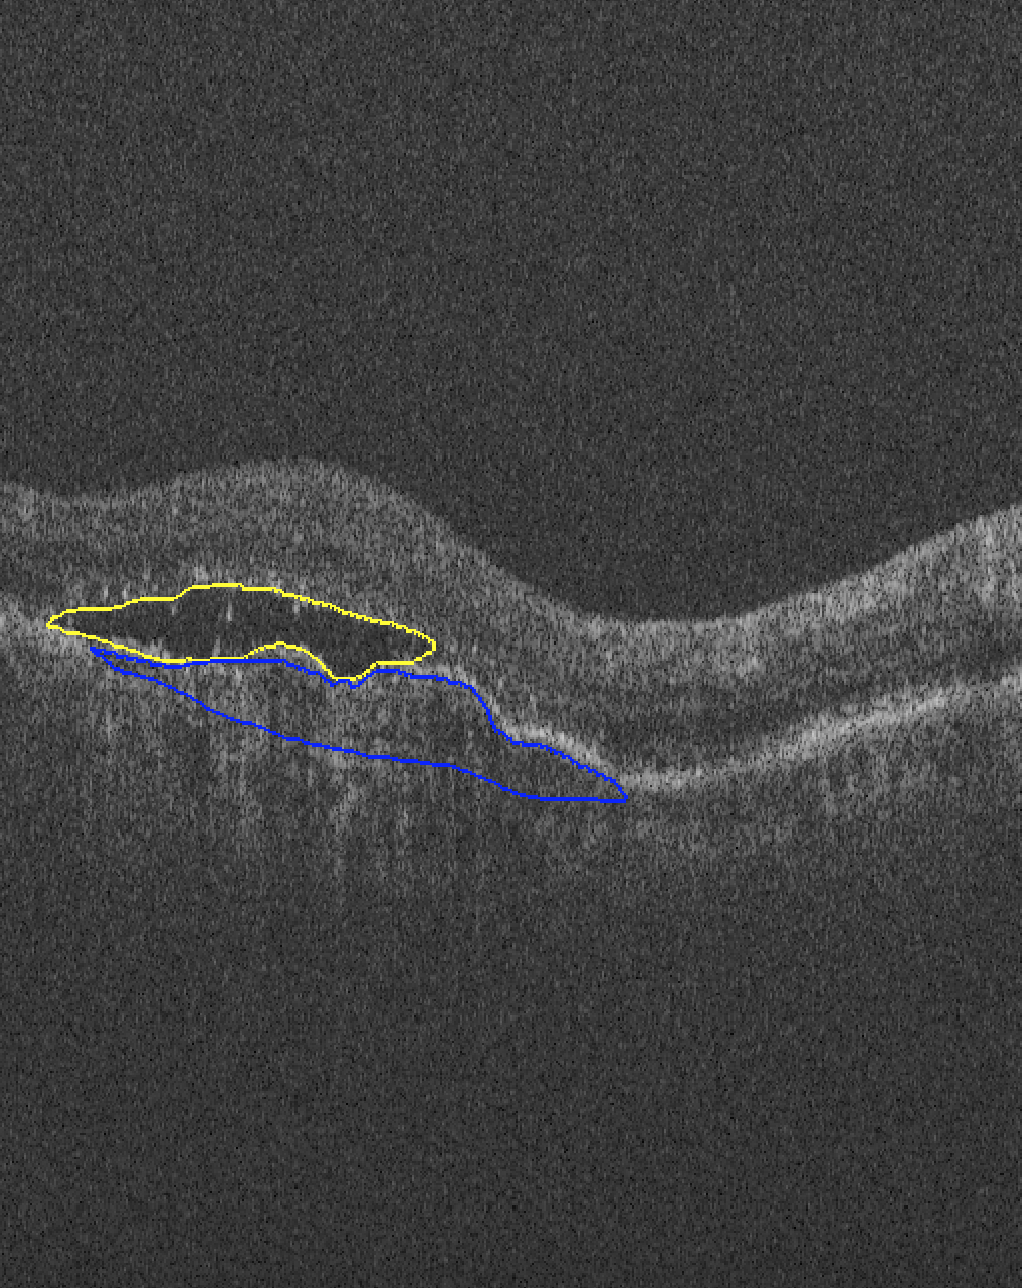

The images used in this study are provided by the MICCAI RETOUCH Group[1]. There were 3 training data sets and a total of 70 volumes, with 24 volumes acquired with each of the two OCT imaging devices: Cirrus (Zeiss) and Spectralis (Heidelberg), and 22 volumes acquired with T-1000 and T-2000 (Topcon, collectively referred to by the manufacturer name in the rest of paper). For each volume from these three devices, the numbers of B-scans were 128, 49 and 128, respectively. Three different types of fluid, namely the intraretinal fluid (IRF), subretinal fluid (SRF) and the pigment epithelial detachment (PED) were manually labeled and provided as ground truth. Although not all B-scans contained fluid, there was at least one type of fluid in each volume. Topcon images with and without macular edema are shown in Fig 1 for each commercial device.

| (a) Cirrus | (b) Spectralis | (c) Topcon |

| (3) | ||||

Both Dice and AVD were computed per volume. For each type of fluid, the segmentation was measured separately, and volumes which doesn’t contain this type of fluid were ignored for its measurement. The mean and standard deviation of AVD is presented in Table 1 and the Dice index was displayed in Fig 3. The red indicates outliers that were caused by two reasons: 1) the volume only contained a very small area of fluid and the proposed method failed to detect it, such as left panel in Fig 4; 2) the retina was warped too much, such as right panel in Fig 4 due to extremely severe disease and the proposed method could not recognize all of the fluid pixels, as there was no similar volume with which to train the network in the leave-one-out experiment.